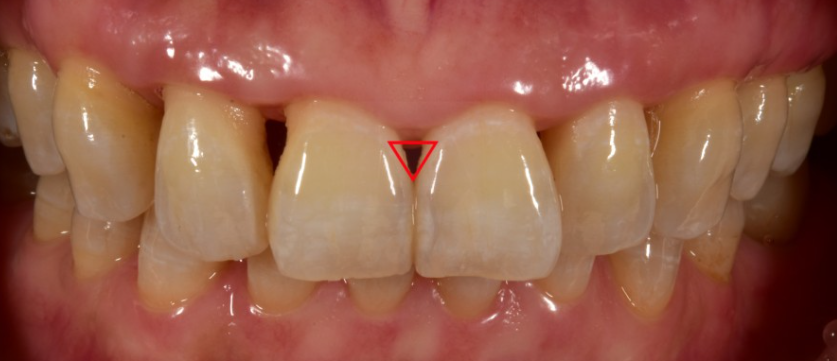

앞니 충치뿐만 아니라,

치아 사이 틈이 벌어지면 까맣게 보이는

블랙 트라이앵글이라고 불리는 치아 빈틈을

심미치료로 라미네이트

시술을 진행하기도 합니다.

블랙트라이앵글의 크기가 커지면

커질수록 치아 사이에 이물질이 끼여

충치로 발전할 가능성 또한 높기 때문에

심미치료로 무삭제라미네이트 블랙필름

시술을 많이 진행하고 있습니다.